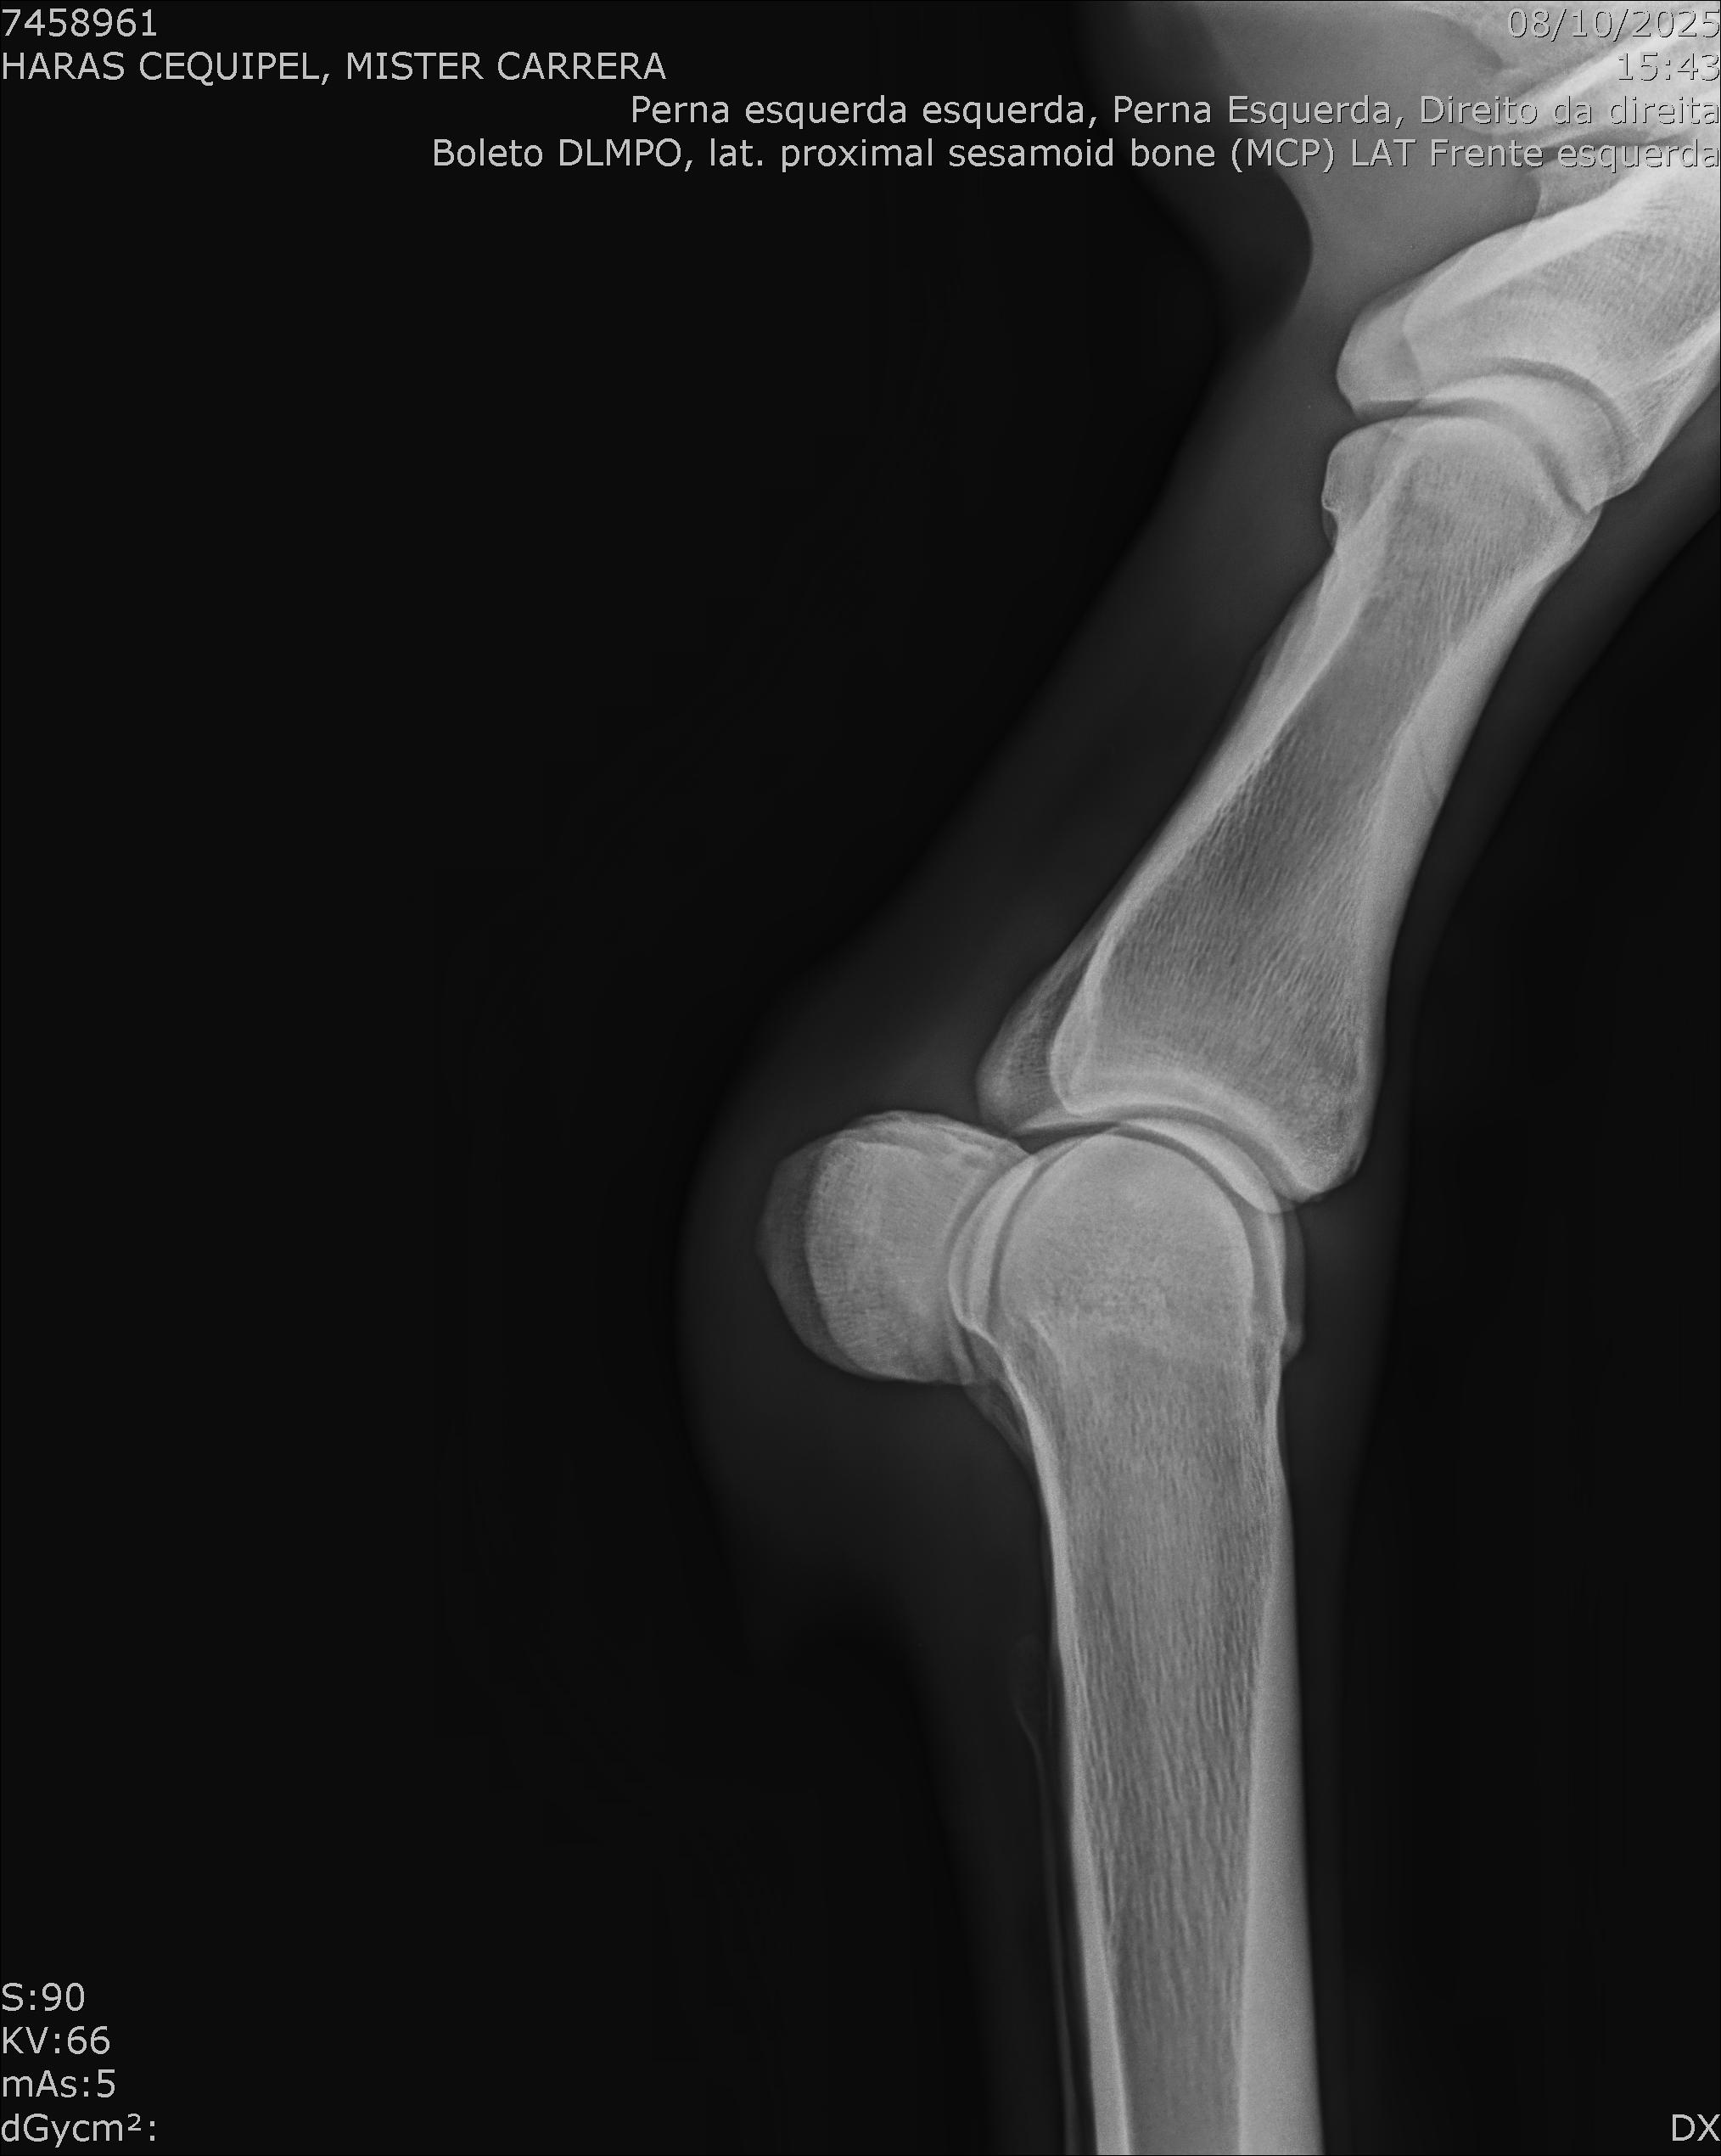

:: RAIOS-X DO LOTE